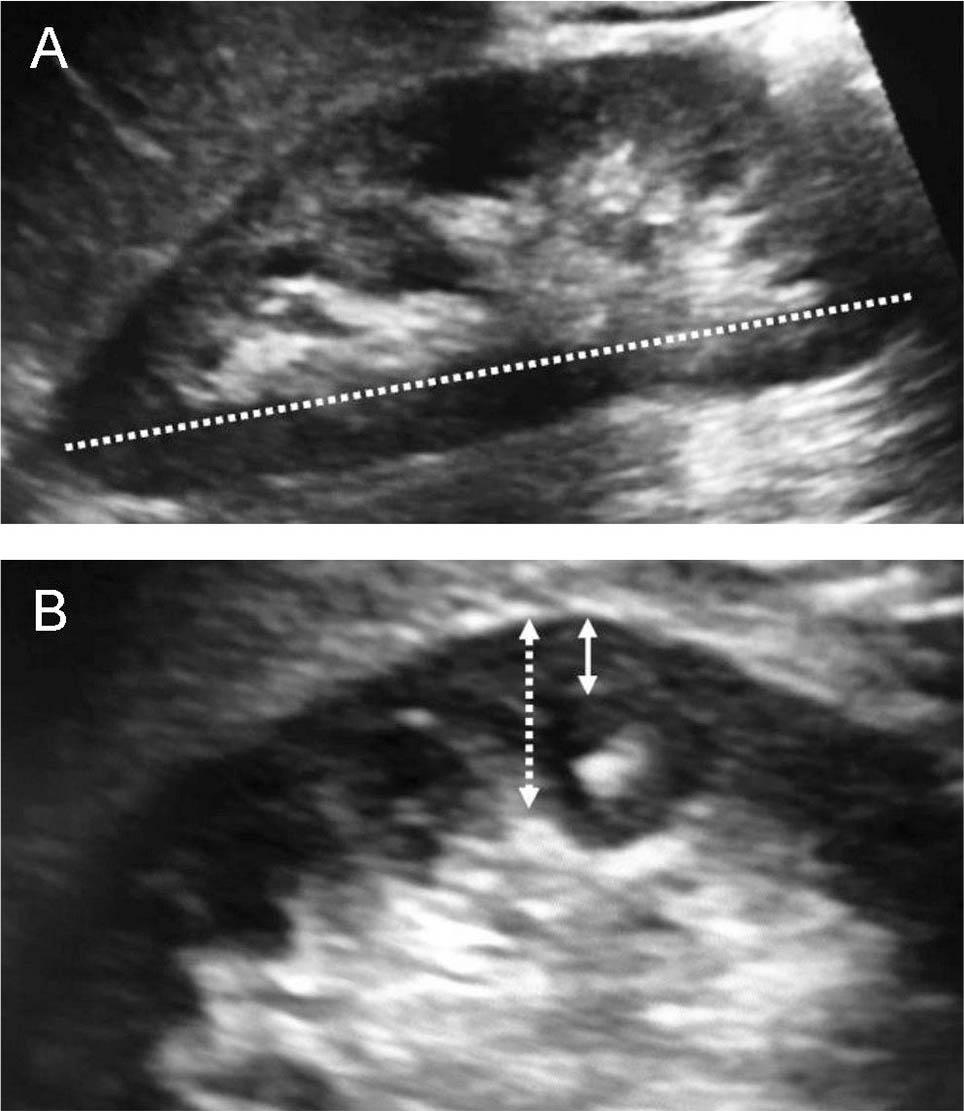

Ultrasound renal measurements obtained from a frozen image: pole-to-pole length or the absolute RL measured to the nearest millimeter (Figure 1A), the renal PT was measured from the renal hilar fat-parenchymal interphase to the maximum outer convex border of the kidney, to the nearest 0.1 mm. RCT was measured over a medullary pyramid, from the corticomedullary interphase to the renal capsule, perpendicular to the renal capsule, to the nearest 0.1 mm (Figure 1B). Both parenchymal and cortical thicknesses were measured in the mid-region of the kidney, parallel to each other and perpendicular to the longitudinal renal measurement using a magnified frozen image. All ultrasound measurements were recorded 3 times, and the average of these was taken for calculations. The relative RL was calculated: the absolute length (in mm) divided by the height of the patient (in cm); expressed in mm/cm.

Representative ultrasound images of the kidney. A. Showing absolute renal length (RL) measurement. The white dotted line indicates the absolute RL. B. Showing cortical and parenchymal thickness measurements. The white dotted arrow indicates the renal parenchymal thickness; white solid arrow indicates renal cortical thickness.